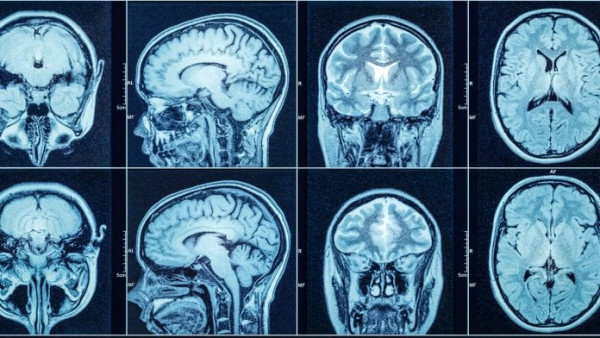

Η βαριά Covid-19 προκαλεί τη συσσώρευση παθολογικών πρωτεϊνών στον εγκέφαλο. Ο ιός δεν αποκλείεται να αυξάνει τον κίνδυνο άνοιας, όμως αυτό δεν είναι ακόμα σαφές.